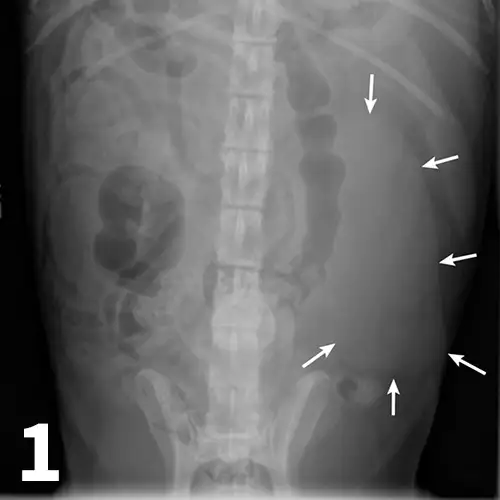

Survey abdominal radiographs (Figures 1 and 2) offer important information on kidney number, size, shape, symmetry, and location, as well as the presence of any mineralized opacities (eg, calcified tissue, nephroliths). The utility of abdominal radiographs is decreased in patients with abdominal fluid or lack of abdominal fat (eg, young or emaciated patients) because of lack of contrast. Excretory urography (IV pyelography), although more invasive, can augment survey radiographs and provide information about renal parenchymal architecture (eg, filling defects associated with cysts or infiltrative disease), the renal pelvis, and ureters as well as a qualitative assessment of global and individual renal excretory function (Figure 3).

Figure 1.

An enlarged left kidney with an irregular shape (arrows) is noted on the VD view of a dog with renal adenocarcinoma. The left kidney measured 4.5 times the length of L2; normal kidney length in the dog is 2.5 to 3.5 times the length of L2.